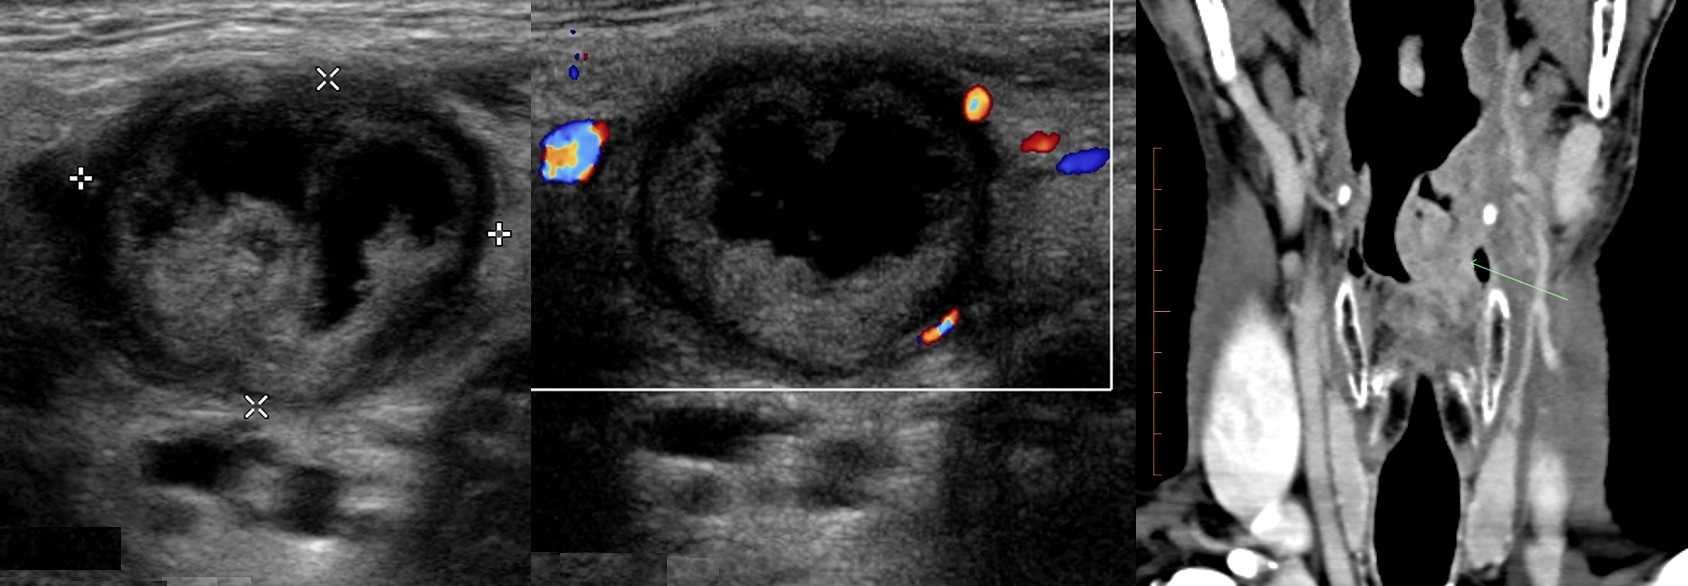

Рисунок. На УЗИ лимфоаденопатия с эхо-признаками злокачественного процесса: увеличенный (28х16 мм) лимфоузел, округлой формы (Д/К <2), гипоэхогенный без центрального рубчика; определяется подкапсульный кровоток, диаметр сосудов не уменьшается по направлению к капсуле, RI 0,88.

Рисунок. Мужчина 63-х лет обнаружил «опухоль» на шее: растет медленно без боли и лихорадки. На УЗИ в районе кивательной мышцы определяется группа резко гипоэхогенных лимфоузлов без центрального рубчика, размер 10-20 мм; часть лимфоузлов округлые; встречаются лимфоузлы с резко усиленным кровотоком. Заключение по результатам биопсии: Лимфома.

Рисунок. Женщина 32-х лет с «опухолью» на шее. На УЗИ в левой надключичной области определяются один большой и несколько маленьких гипоэхогенных лимфоузлов, округлой формы, центральный гиперэхогенный рубчик тонкий; кровоток заметно усилен, сосуды расположены хаотично, диаметр не уменьшается по направлению к капсуле, выраженный подкапсульный кровоток. В левой подвздошной ямке видно «сэндвич» — конгломерат из увеличенных гипоэхогенных лимфоузлов, между которыми залегают сосуды брыжейки. Заключение: Лимфоаденопатия с эхо-признаками злокачественного процесса. Рекомендована биопсия измененных лимфоузлов.

Рисунок. Мужчина 50-ти лет с жалобами на осиплость голоса, «опухоль» на шее слева. На УЗИ на шее определяется круглое образование с большой анэхогенной полостью в центре — зона некроза. На КТ видно большую опухоль в надгортанной области слева. Заключение по результатам биопсии: Увеличенный лимфоузел с метастазами плоскоклеточного рака. Для плоскоклеточного рака типичен центральный некроз лимфоузлов.